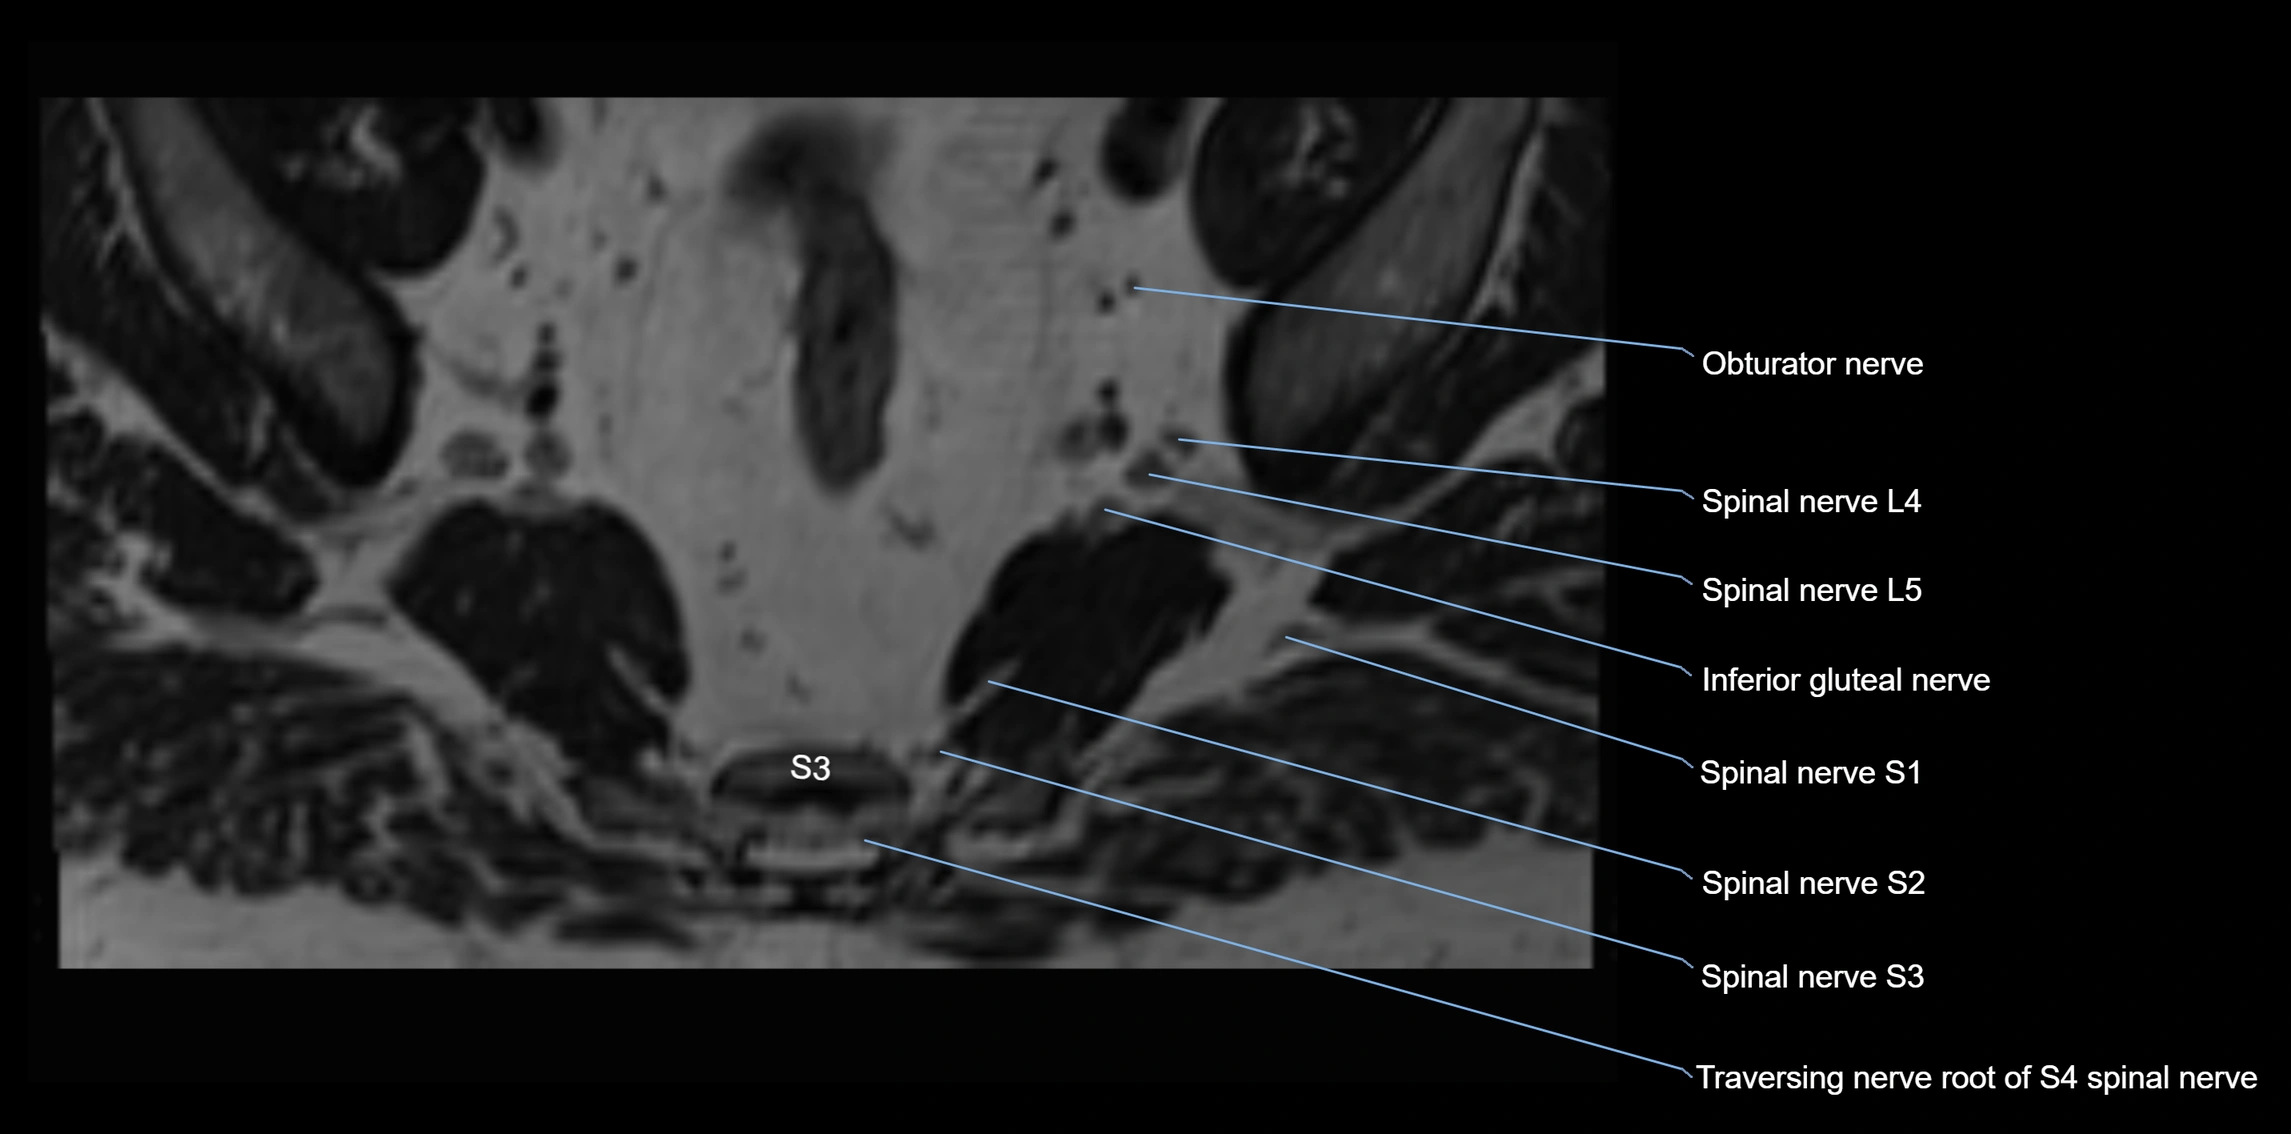

MRI image

image